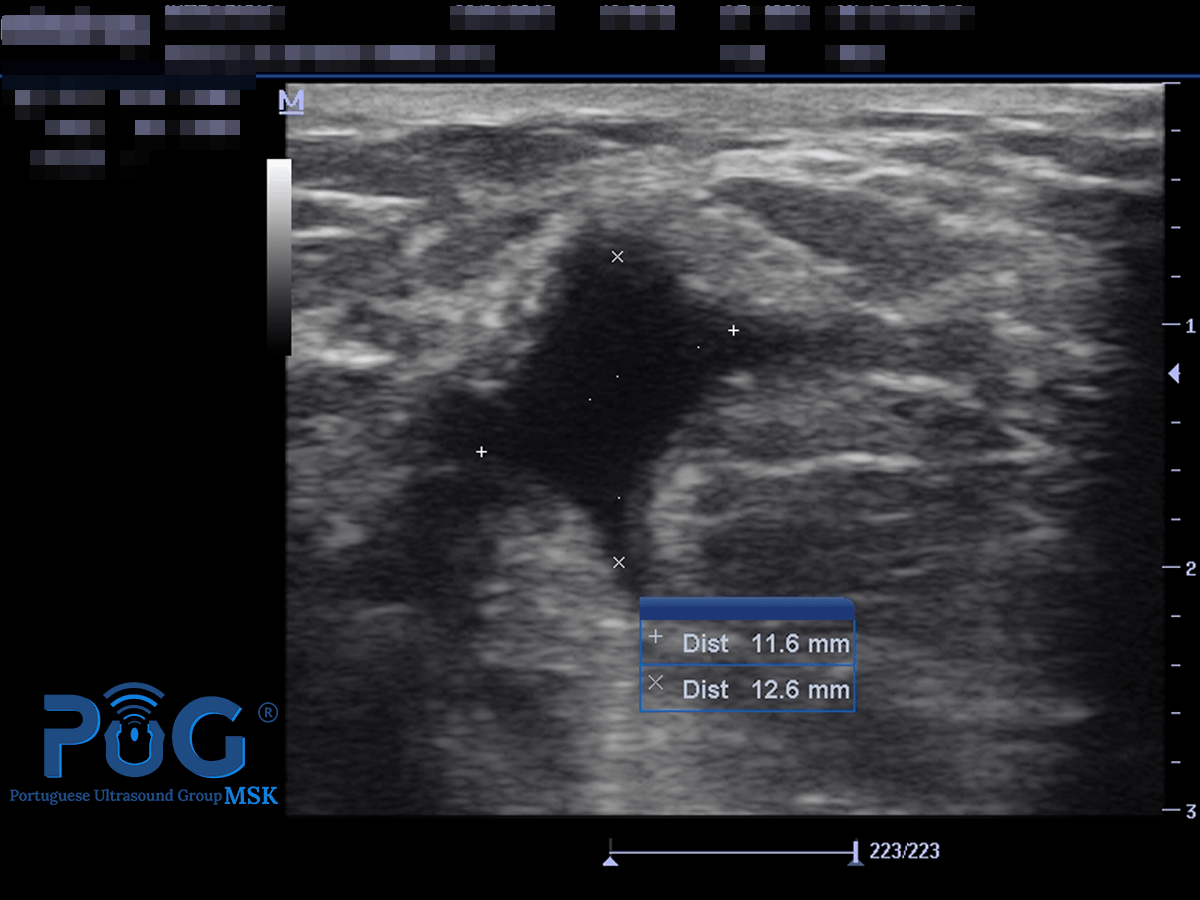

Imagem ecográfica de uma tendinopatia.

Ecografia de uma tendinopatia rotuliana crónica e neoneurovascular

Por Dr. José Manuel Sánchez 01 ago, 2019

Nas tendinopatias degenerativas, para além da degradação de colagénio, degeneração mixóide, défice de mobilidade fluídica da matriz extracelular (MEC), e da morte celular, devemos considerar a importância de outra característica patogénica. Existe, de forma significativa, uma hipóxia (baixo teor de oxigénio), no tendão que provoca uma resposta inflamatória persistente.